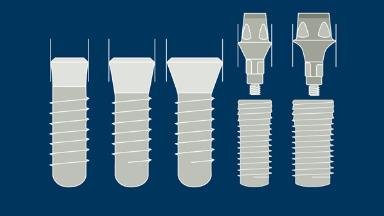

- describe variations in the implant prosthodontic interface

- describe variations in the implant transmucosal section

- describe variations in the implant endosseous part